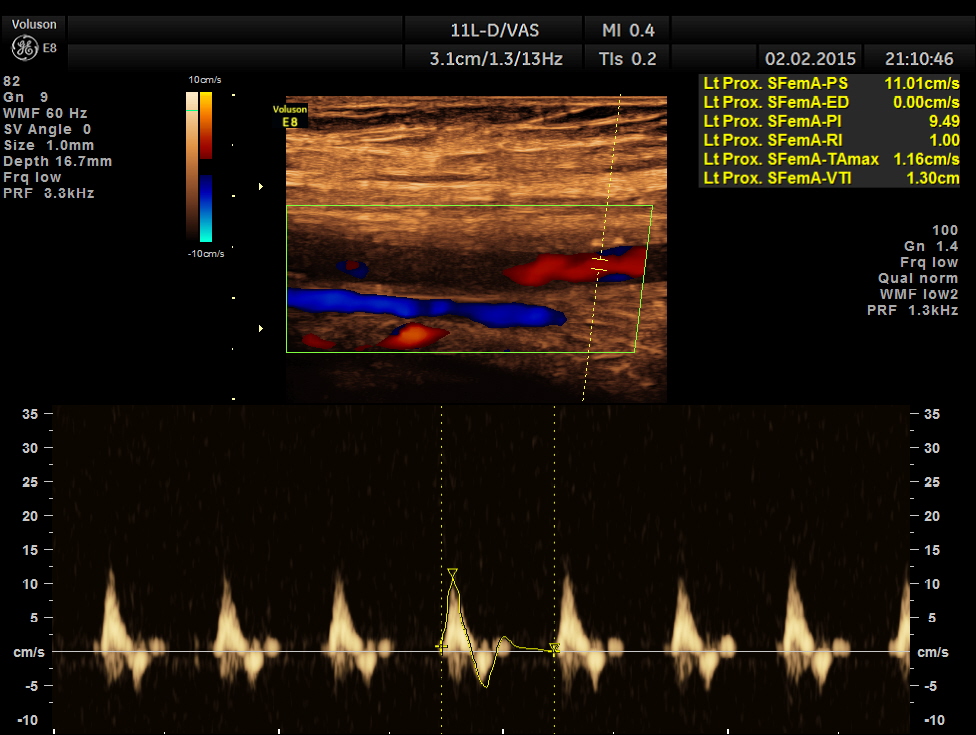

left proximal superficial femoral artery shows reduced peak systolic velocity

the following pictures show progressive fall of peak systolic velocity with no flow made out in the distal superficial femoral artery.